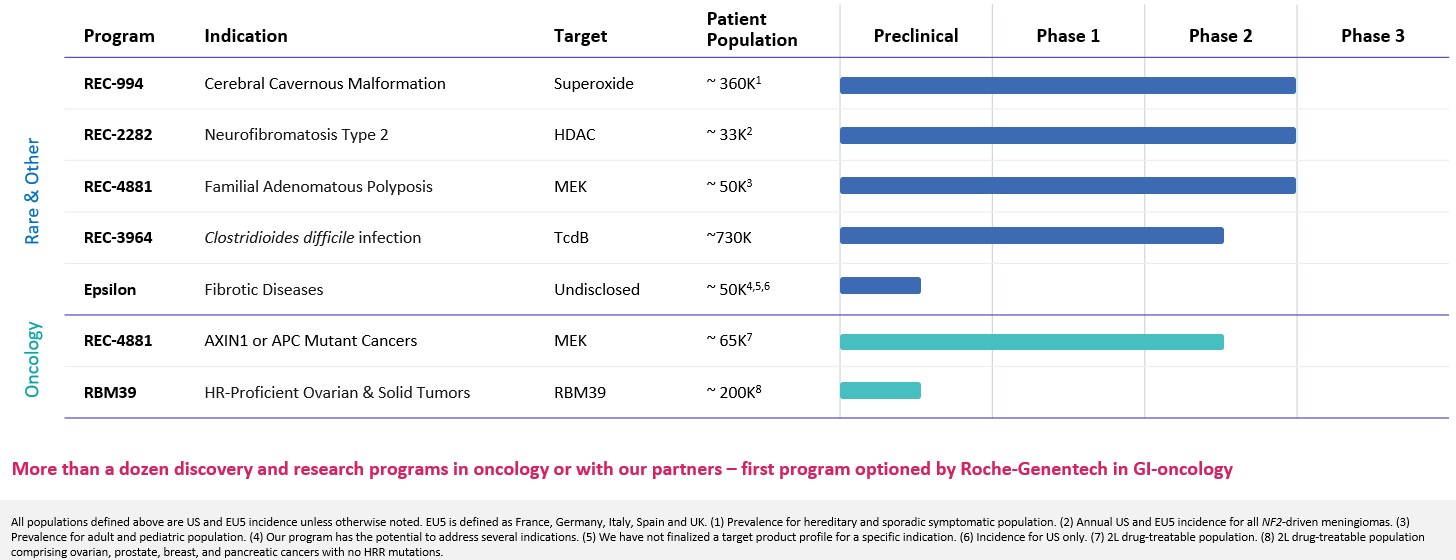

| | What’s more, the signs of AI-enabled point-solutions are already plentiful across our industry: •Protein folding •Scaled protein-ligand interaction prediction •Generative AI for chemistry for tractable targets •The FDA is already discussing the use of LLMs for program review •Major pharma companies are drafting regulatory filings like INDs by LLMs These facts lay out a clear future where efficiencies and improvements across the many current AI-enabled point-solutions will begin to combine into integrated ‘tech-stacks’ and workflows that will result in compounding improvements in our ability to drug historically undruggable targets, understand the underlying networks of biology with increasing fidelity, fast-follow newly validated biology, characterize disease in increasingly robust ways and ultimately deliver more, better medicines to patients to alleviate suffering at scale. The question is no longer whether this sort of future is before us, but when and who will lead it. Looking Back at 2023 and Before Reflecting back on late 2013 when Recursion was founded and how far we have come, it is simultaneously incredible and unsurprising to see where we are today. Recursion was then a Utah-based startup founded by two graduate students and a professor. Our first office was a conference room in the nearby University Research Park and our first laboratory was a converted storage room. Today, Recursion is a multinational, clinical-stage company leading the transition of BioTech into TechBio. We have over 500 employees, five clinical stage programs, one of the world’s largest biological and chemical datasets and two of the largest discovery collaborations in the industry with Roche/Genentech and Bayer. And in 2023, the opportunity ahead feels so much greater than it did in 2013, that in some ways it still feels like we are just getting started. In fact, from an internal perspective, 2023 felt like one of the best years in our history. In 2023 we achieved a lot of important milestones, and a lot of things we’ve been working to build, in some cases for years, really seemed to start hitting their stride, including: Pipeline •Five phase 2 clinical-stage programs with multiple upcoming data readouts expected, including REC-994 in cerebral cavernous malformation (CCM) in Q3 2024, REC-2282 in neurofibromatosis type 2 (NF2) in Q4 2024, REC-4881 in familial adenomatous polyposis (FAP) in H1 2025, and REC-4881 in AXIN1 or APC mutant solid tumors in H1 2025 •Completed a Phase 1 study for REC-3964 in healthy volunteers for the potential treatment of Clostridioides difficile (C. difficile) infection with a favorable safety and tolerability profile •Advanced our RBM39 program in homologous recombination proficient ovarian cancer and other solid tumors to IND-enabling studies •In-licensed a program (Target Epsilon) that emerged from our fibrosis collaboration with Bayer that represents a novel approach to treating fibrotic diseases with compelling early data |

•Five phase 2 clinical-stage programs with multiple upcoming data readouts expected, including REC-994 in cerebral cavernous malformation (CCM) in Q3 2024, REC-2282 in neurofibromatosis type 2 (NF2) in Q4 2024, REC-4881 in familial adenomatous polyposis (FAP) in H1 2025, and REC-4881 in AXIN1 or APC mutant solid tumors in H1 2025

•Completed a Phase 1 study for REC-3964 in healthy volunteers for the potential treatment of Clostridioides difficile (C. difficile) infection with a favorable safety and tolerability profile

•Advanced our RBM39 program in homologous recombination proficient ovarian cancer and other solid tumors to IND-enabling studies

•In-licensed a program (Target Epsilon) that emerged from our fibrosis collaboration with Bayer that represents a novel approach to treating fibrotic diseases with compelling early data